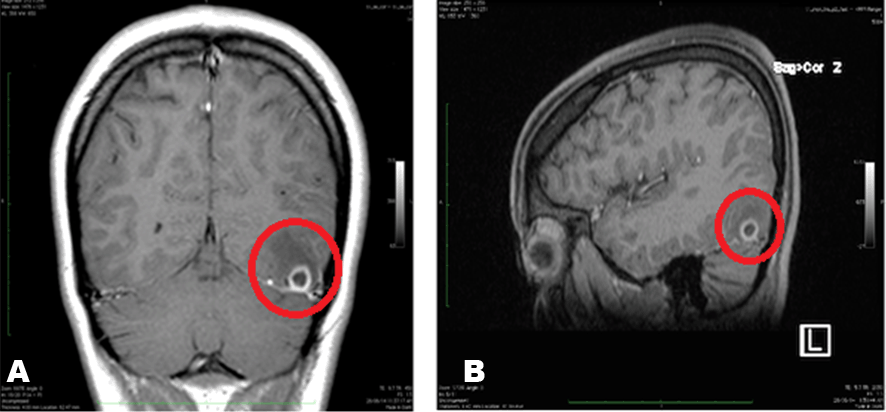

Due to a higher possibility of an infectious etiology, MRI of brain was ordered. MRI demonstrated a well-defined ring enhancing cystic lesion in subcortical basal occipital lobe with eccentric poorly enhancing calcified scolex with perilesional edema suggesting granulomatous NCC as shown in Figure 1(A and B) . Blood tests revealed elevated IgE levels along with (+) CSF ELISA testing. Awake EEG was performed with interictal bilateral frontal temporal spike wave epileptiform discharges although no discharges were noted during photic stimulation with uneventful sleep recordings as well. Stool culture and analysis was positive for adult tapeworms. Consequently, patient was started on Phenytoin, then switched to Valproic Acid for seizure control. In addition, patient was started on Albendazole for one year with initial follow up every two weeks for first six months. During initial follow up patient had no recurrent seizures. In addition, patient has been seizure free for more than one year after initial treatment. In addition, patient has regularly followed up with good medication compliance, improved personal hygiene and returning to a vegetarian diet.

Figure 1 (A and B): Coronal and sagittal views of ring-enhancing lesion with surrounding edema demonstrating a supratentorial cystic mass on the left side along with enhancing ring.